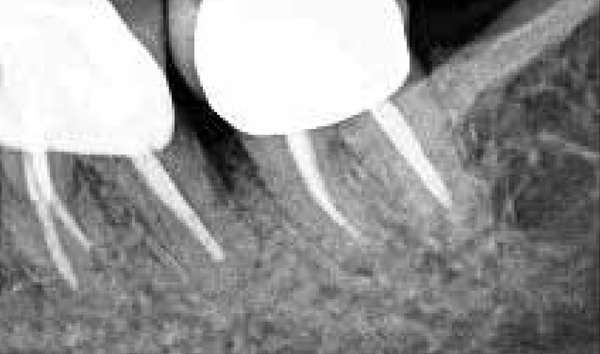

The consensus report from the AAP's workshop group on intrabony defects presents evidence that periodontal regeneration in intrabony defects is possible on previously diseased root surfaces, demonstrated by gains in clinical attachments, reductions in periodontal pocket depths, gains in radiographic bone heights, and overall improvements in periodontal health.9 These clinical findings are consistent with available histologic evidence, and the clinical improvements can be maintained over long periods of time (ie, > 10 years).9 Although bone replacement grafts have been a commonly investigated modality, guided tissue regeneration, biologics, and combination therapies have also been shown to be effective. Early management offers the greatest potential for successful periodontal regeneration.9 Figure 9 through Figure 11 depict the treatment of a tooth with probing depths of equal to or greater than 15 mm using mineralized FDBA.

(9.) Pretreatment radiograph of tooth with probing depths of equal to or greater than 15 mm.

Figure 9

(10.) Intrasurgical photograph of treatment with mineralized FDBA and EMD.

Figure 10

(11.) Postoperative radiograph taken 4 years after treatment, demonstrating 3- to 4-mm probing depths.

Figure 11